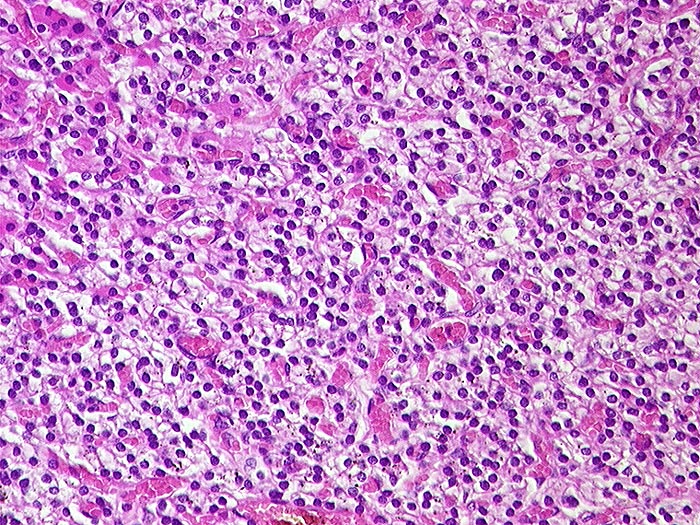

Sekundärer Hyperparathyreoidismus: Hauptzell-Hyperplasie

Hauptzellen mit klarem Zytoplasma und kleinen runden Kernen. Fehlendes Fettgewebe.

Dialyse seit Jahren bei terminaler Niereninsuffizienz wegen Analgetikanephropathie.